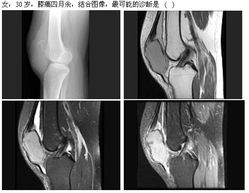

1. 设备升级,诊断精准:医院引进了先进的数字化X射线摄影系统(DR)等放射诊疗设备。相比传统设备,新设备具有成像速度快、图像清晰度高、辐射剂量更低等优势,能够为临床医生提供更精准的影像诊断依据,尤其有助于常见病、多发病及部分慢性病的早期发现与诊断。